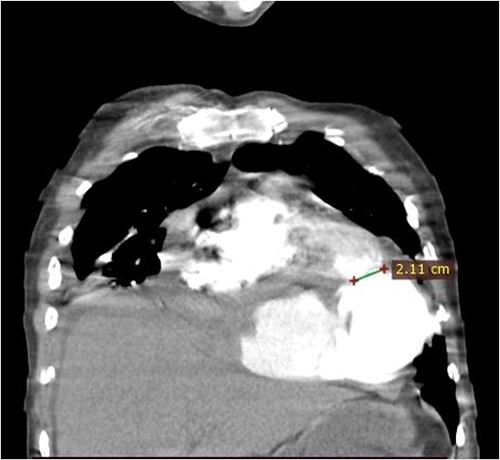

A 46-year-old man from rural Ethiopia was referred 7 days after he started to have sudden shortness of breath, chest pain and cough. On 6th day of his symptoms, he had brief loss of consciousness and left-sided body weakness. When he arrived to our hospital on 7th day of symptom onset, his vitals were: blood pressure 100/70 mmHg, pulse rate 104–112 beat/min, respiratory rate 24 breaths/min, SpO2 95% on room air. There was Grade 3 systolic murmur at the apex. Power of left upper and lower extremities was 3 and 4 out of 5, respectively. Laboratory tests were white cell count of 15 800, with 89% neutrophils, hemoglobin of 11.4 g/dl, platelet count of 180 000, INR of 2.2. Cardiac markers and Electrocardiogram (ECG) were normal. Echocardiography showed 19 mm defect at apex of left ventricle with bidirectional flow between ventricular chamber and pseudoaneurysmal septated intrapericardial collection. Chest CT revealed huge pseudoaneurysm (contained rupture) the communicates with left ventricle via a 2.1 cm rupture (see Figs 1 and 2). Patient’s medical history was relevant for unprovoked deep venous thrombosis (DVT) of left lower extremity a year back, which was treated with warfarin.

Coronal CT scan image. The figure shows a 2.1 cm communication between left ventricle and pseudoaneurysm. The heart is pushed upwards.